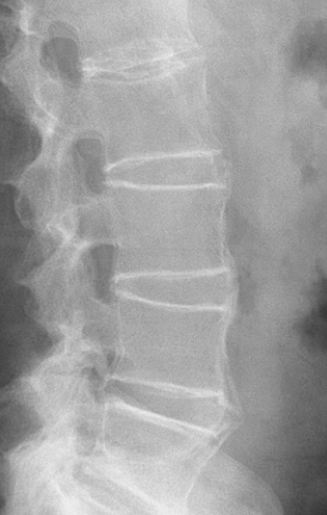

What imaging is useful in dx ank spon?